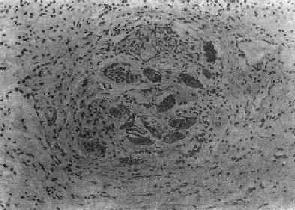

第二节 血吸虫病血吸虫病(schistosomiasis)是由血吸虫寄生于人体引起的地方性寄生虫病。寄生于人体的血吸虫主要有三种:即流行于非洲北部的埃及血吸虫(Schistosoma haematobium);流行于拉丁美洲及非洲中部的曼氏血吸虫(Schistosoma mansoni)以及流行于亚洲的日本血吸虫(Schistosoma japanicum)。在我国因只有日本血吸虫病流行,故通常将日本血吸虫病简称为血吸虫病。 根据1972年在湖南长沙马王堆一号墓出土的西汉女尸及1975年在湖北江陵出土的西汉男尸内皆发现有大量典型血吸虫卵的事实,证明在2100多年前我国已有血吸虫病的流行。本病在我国主要流行于长江流域及其以南的十三个省市的广大水稻作物地区,尤以江苏、浙江、安徽、湖北、湖南、江西等省及上海市效较为严重。过去本病流行猖獗,对广大劳动人民的健康危害极大。新中国成立后,积极发展了防治工作,广东、广西、福建、江苏和上海等五个省市和全国270多个县已基本消灭了血吸虫病。 【病因及感染途径】 日本血吸虫的生活史可分为虫卵、毛蚴、胞蚴、尾蚴、童虫及成虫等阶段。成虫以人体或其他哺乳动物如狗、猫、猪、牛及马等为终宿主,自毛蚴至尾蚴的发育繁殖阶段以钉螺为中间宿主。 血吸虫虫卵随同病人或病畜的粪便排入水中,卵内的毛蚴成熟孵化,破壳而出,以后钻入钉螺体内,经过母胞蚴及子胞蚴阶段后,大量尾蚴发育成熟,并游动于水中。当人畜与疫水接触时,尾蚴借其头腺分泌的溶组织酶作用和其肌肉收缩的机械运动,很快钻入皮肤(或粘膜)并脱去尾部变为童虫。童虫经小静脉或淋巴管进入血液循环,再经右心而到达肺。以后由肺的毛细血管经肺静脉而入大循环向全身散布。只有进入肠系膜静脉的童虫,才能继续发育为成虫,其余多在途中夭折。通常在感染尾蚴后3周左右即可发育为成虫,雌雄成虫交配后即可产卵。虫卵随门静脉血流顺流到肝,或逆流入肠壁而沉着在组织内,约经11天左右逐渐发育为成熟虫卵,内含毛蚴。肠壁内的虫卵可破坏肠粘膜而进入肠腔,并随粪便排出体外,再重演生活周期。虫卵在组织内的寿命约为21天左右。雌雄合抱的成虫在人体内的寿命一般为3~4年。 【病变和发病机制】 血吸虫发育阶段中的尾蚴、童虫及成虫、虫卵等均可引起病变,但以虫卵引起的病变最严重,危害也最大。 1.尾蚴及童虫引起的病变 (1)尾蚴性皮炎:尾蚴侵入皮肤后,可引起皮肤的炎症反应,称为尾蚴性皮炎(cercarial dermatitis)。多发生于重复感染的患者,一般在尾蚴钻入皮肤后数小时至2~3日内发生,表现为红色小丘疹,奇痒,经数日后可自然消退。镜下见真皮充血、出血及水肿,起初有中性及嗜酸性粒细胞浸润,以后主要为密集的单核细胞浸润。 目前认为本病的发病机制主要与迟发性变态反应有关。动物实验证明,转移感染小鼠的淋巴细胞给正常小鼠,再接种尾蚴,经1~2天,局部童虫周围有单核细胞浸润。在反应早期可能有抗体介导的免疫反应参与。 (2)肺部病变:童虫移行到肺时,部分可穿破肺泡壁毛细血管,游出到肺组织中,引起点状出血及白细胞浸润(约在感染后1~2天)并可有血管炎改变,但病变一般轻微而短暂。 童虫经大循环移行到其他器官时也可引起与肺类似的改变。 童虫所引起的各器官点状出血除与童虫的机械作用有关外,还与其代谢产物或虫体死亡后蛋白分解产物所致人体组织的变态反应有关。 宿主感染血吸虫后得到获得性免疫,对再感染产生不同程度的抵抗力。其机制为抗体依赖、细胞介导的细胞毒反应,由IgE或IgG2a抗体,巨噬细胞、嗜酸性粒细胞等参与。主要作用于表面有抗原表达的幼龄童虫,嗜酸性粒细胞有IgG和IgE的Fc受体,当抗体包被童虫后其Fc段与Fc受体结合,并使嗜酸性粒细胞粘附在童虫表面且脱颗粒,释出细胞毒性物质,而起杀伤作用。巨噬细胞也是非常重要的效应细胞。 2.成虫引起的病变 血吸虫在门静脉系统内发育成熟后,其代谢产物可使机体发生贫血、嗜酸性粒细胞增多、脾肿大、静脉内膜炎及静脉周围炎等。在肝、脾的单核吞噬细胞系统的细胞内,常见有黑褐色血吸虫色素沉着,是成虫吞食红细胞后,在虫体内珠蛋白酶作用下,使血红蛋白分解而形成的一种血红素样色素,同样的色素也见于成虫的肠道内。活的成虫本身在静脉内不引起宿主反应,其解释是成虫的表膜内含有宿主的抗原,被宿主认为是“自我”组织而逃避了免疫攻击。成虫死亡后,多在肝内分解,产生毒性,可引起明显的静脉炎和静脉周围炎。死亡虫体周围组织坏死,大量嗜酸性粒细胞浸润,形成嗜酸性脓肿,与血丝虫成虫死亡后引起的变化相似。 3.虫卵引起的变化 虫卵沉着所引起的损害是最主要的病变,虫卵除主要沉着于乙状结肠和直肠壁以及肝外,也常见于回肠末段、阑尾及升结肠等处。肺、脑等其他器官有时也可见到。未成熟的虫卵所引起的病变轻微;含毛蚴的成熟虫卵往往引起虫卵结节形成。按其病变发展过程可分为急性虫卵结节和慢性虫卵结节两种。 (1)急性虫卵结节:肉眼观为灰黄色、粟粒至绿豆大(0.5~4mm)的小结节。镜下见结节中央常有1~2个成熟虫卵,也偶可多达20个以上。这些成熟虫卵的卵壳上附有放射状嗜酸性的棒状体,也称为Hoeppli现象,用免疫荧光法已证实为抗原抗体复合物。虫卵周围是一片无结构的颗粒状坏死物质及大量嗜酸性粒细胞浸润。因其病变类似脓肿,故也称为嗜酸性脓肿(图19-5)。在坏死组织中可混杂多数菱形或多面形屈光性蛋白质晶体,即Charcot-Leyden结晶,系嗜酸性粒细胞的嗜酸性颗粒互相融合而成。随后虫卵周围产生肉芽组织层,其中有以嗜酸性粒细胞为主的炎症细胞浸润,还有单核巨噬细胞、淋巴细胞、浆细胞及少量中性粒细胞。随着病程的发展,肉芽组织层逐渐向虫卵结节中央生长,并出现围绕结节呈放射状排列的类上皮细胞层。类上皮细胞层逐渐加宽,嗜酸性粒细胞显著减少,构成晚期急性虫卵结节(图19-6),这是向慢性虫卵结节发展的过渡阶段。

图19-5 肝血吸虫病之急性虫卵结节 结节中心有一成熟虫卵,卵壳表面可见放射状物质,周围广泛坏死伴大量嗜酸性粒细胞浸润